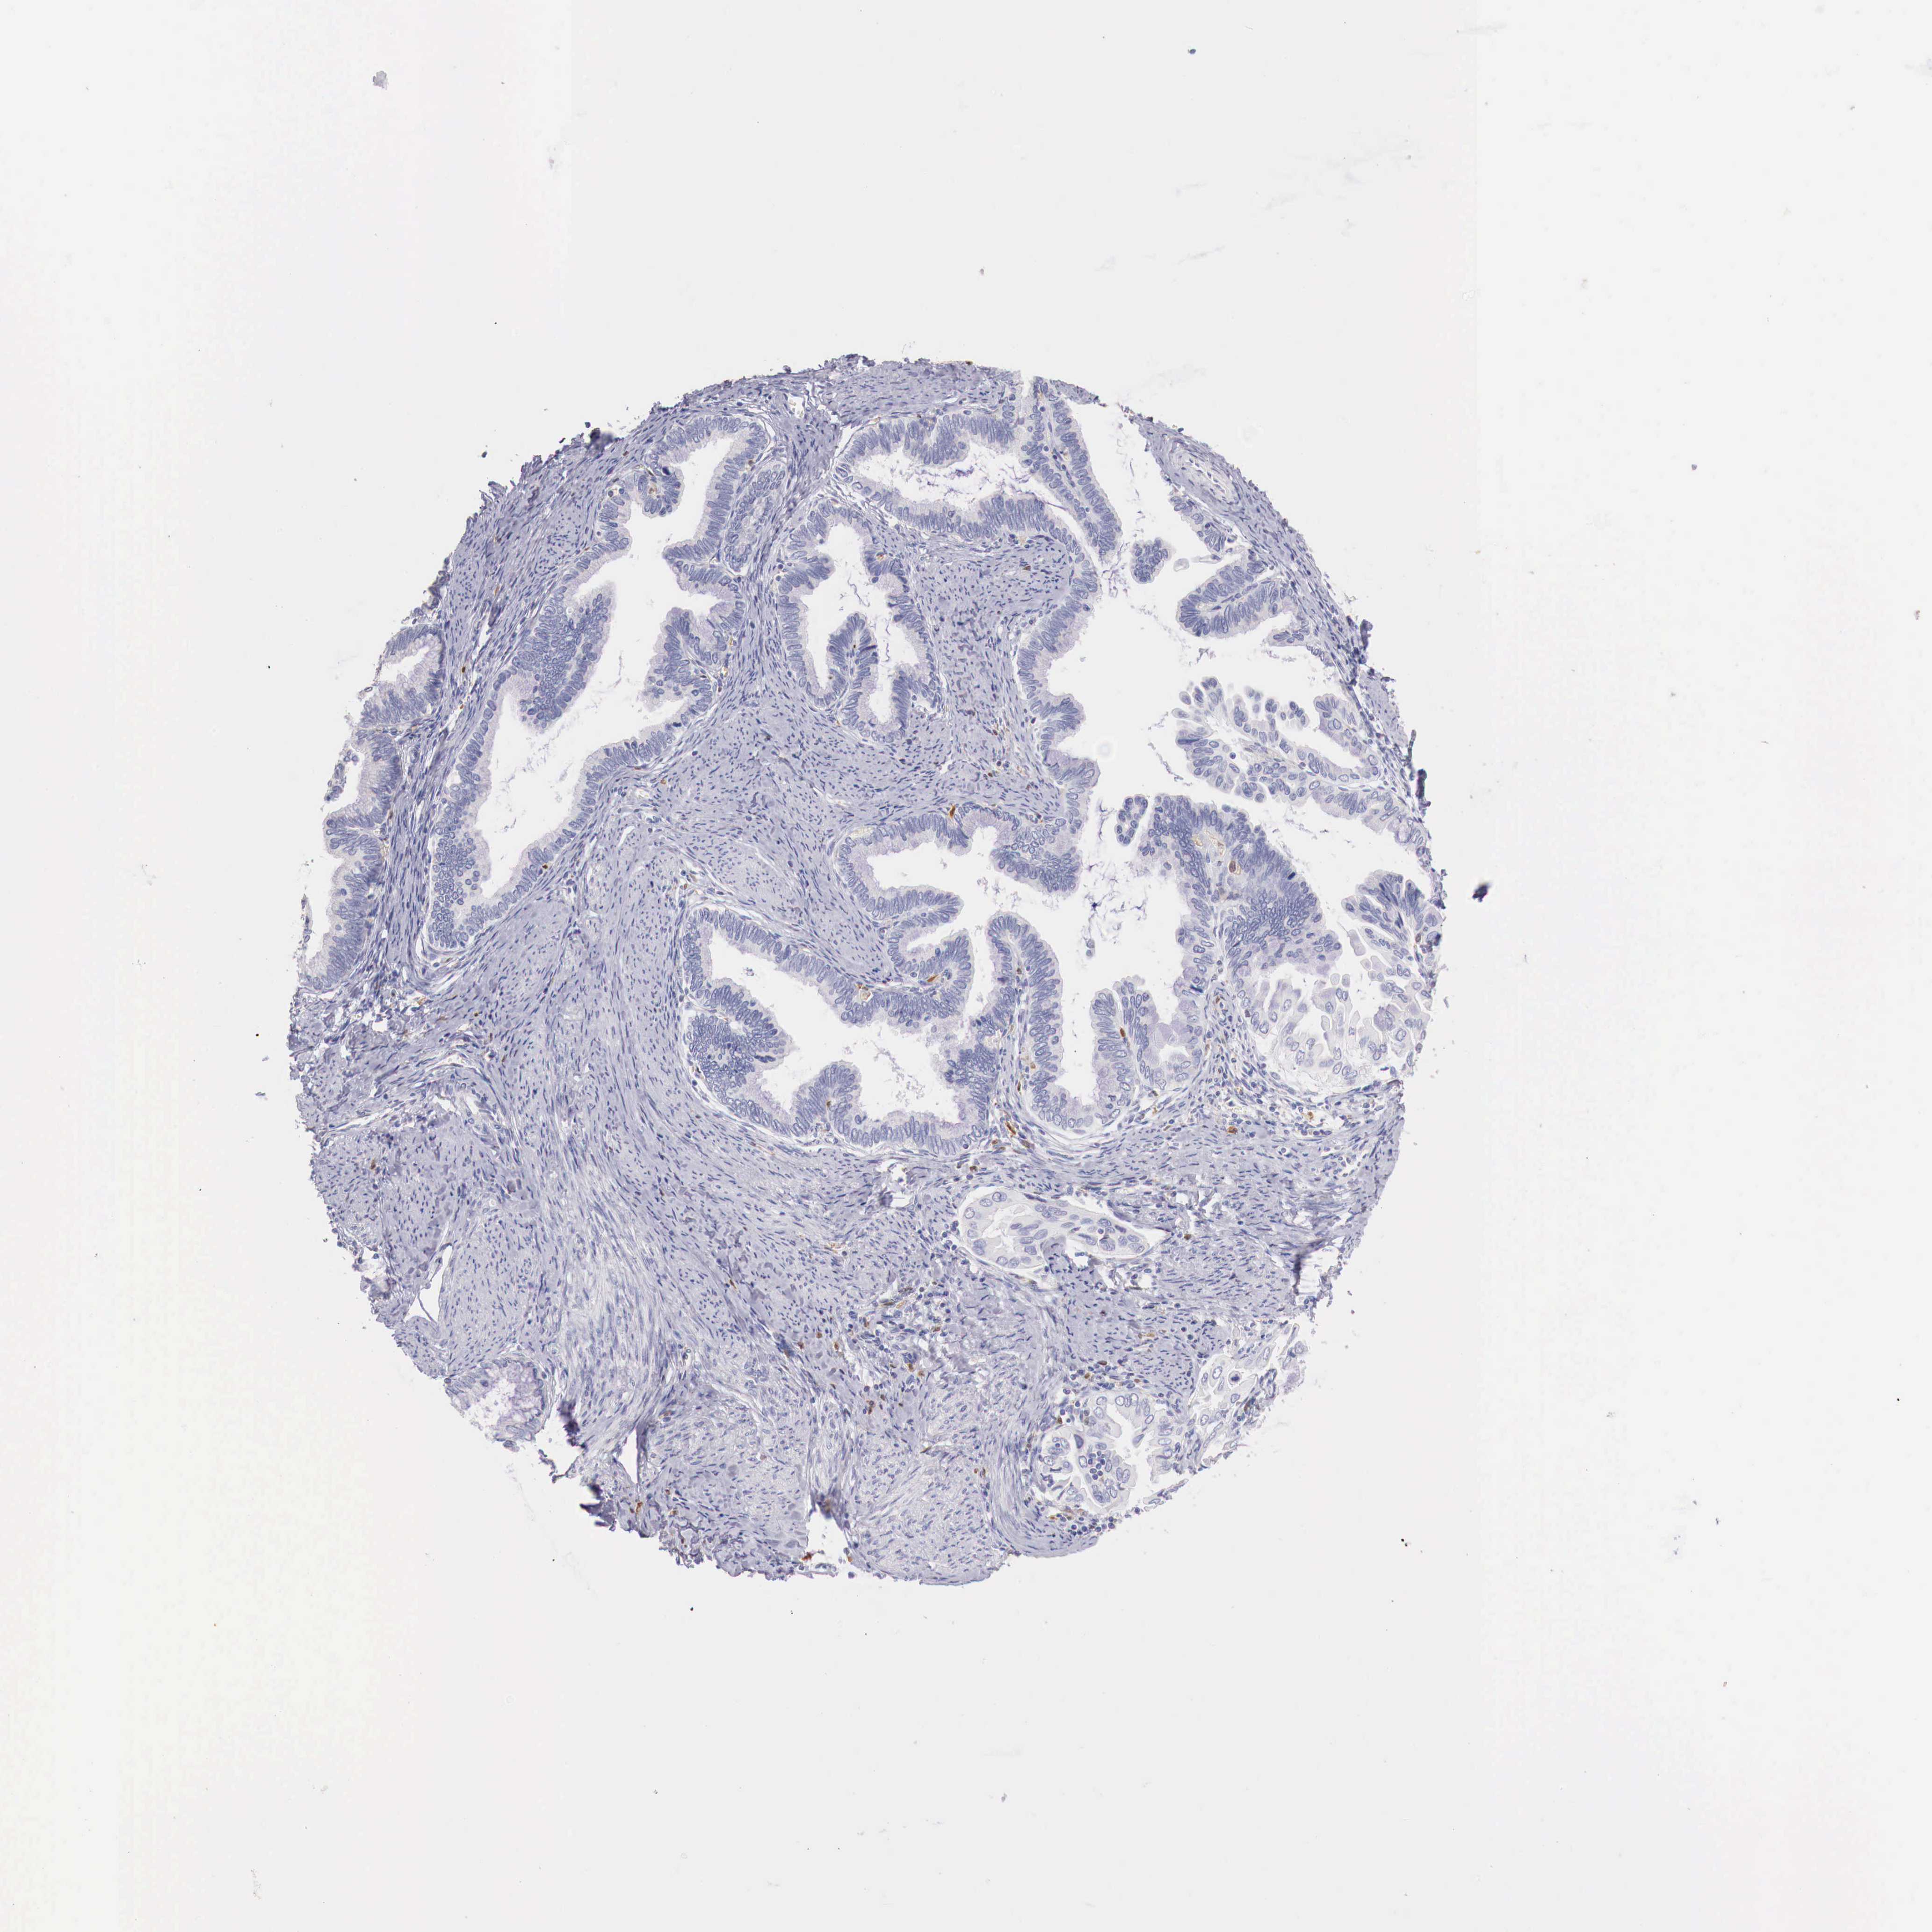

CERVICAL CANCER - Protein expressioni

A mouse-over function shows sample information and annotation data. Click on an image to view it in a full screen mode. Samples can be filtered based on level of antibody staining by selecting one or several of the following categories: high, medium, low and not detected. The assay and annotation is described here.

Note that samples used for immunohistochemistry by the Human Protein Atlas do not correspond to samples in the TCGA dataset.

Antibody stainingi

Antibody staining in the annotated cell types in the current human tissue is reported as not detected, low, medium, or high, based on conventional immunohistochemistry profiling in selected tissues. This score is based on the combination of the staining intensity and fraction of stained cells.

Each image is clickable and will lead to virtual microscopy that enables deeper exploration of all samples and also displays staining intensity scores, fraction scores and subcellular localization as well as patient and tissue information for each sample.

Antibody HPA000428

Antibody HPA000522

Staining

High

Medium

Low

Not detected

Intensity

Strong

Moderate

Weak

Negative

Quantity

>75%

75%-25%

<25%

None

Location

Nuclear

Cytoplasmic/membranous

Cytoplasmic/membranous,nuclear

Adenocarcinoma, NOS

Squamous cell carcinoma, NOS